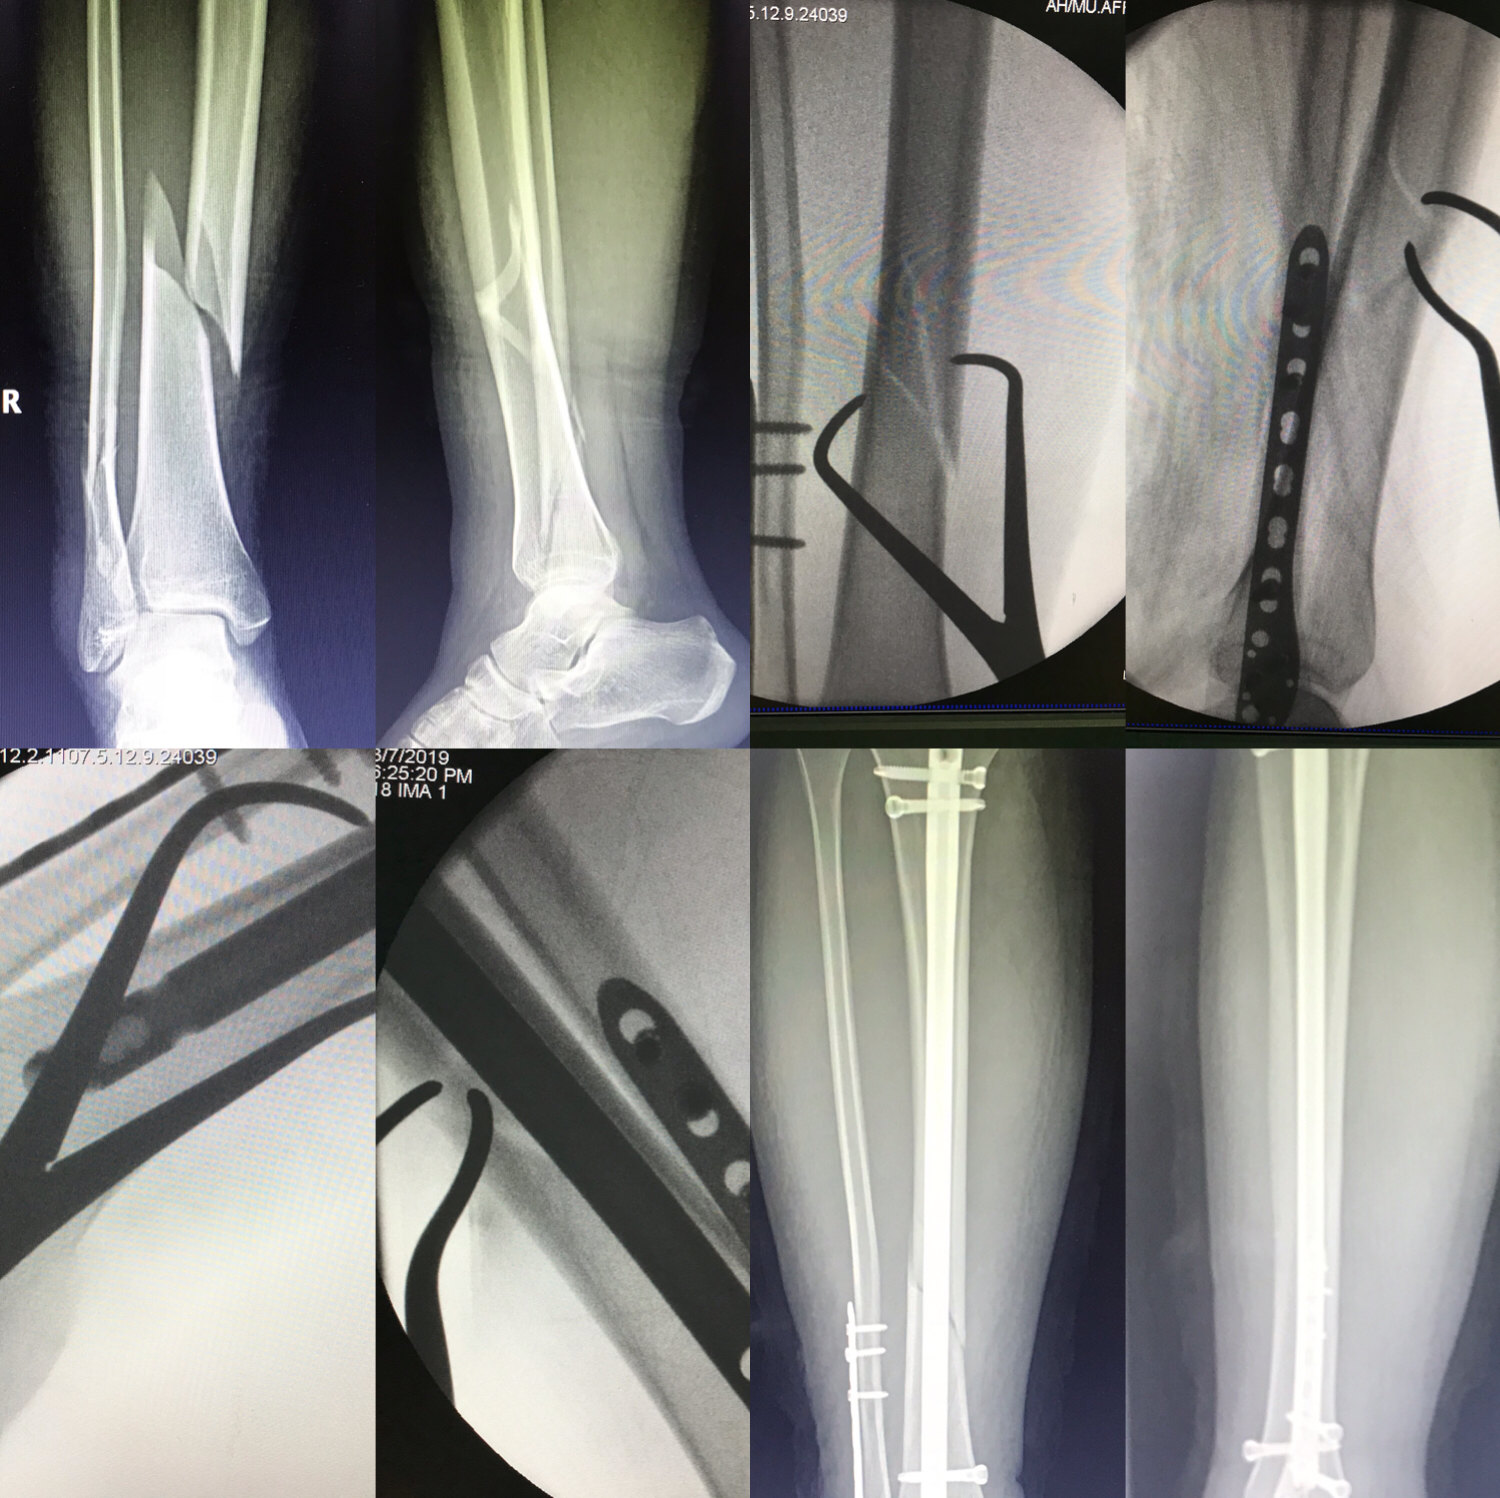

胫骨开放性骨折髓内针固定 骨科与显微外科专业讨论版 爱爱医医学论坛

胫骨骨折髓内钉一例分享 骨科专业讨论版 丁香园论坛

胫骨骨折的微创治疗术后1天抬腿不是梦

骨折微创术 胫骨骨折闭合复位带锁髓内针内固定

Mipo技术微创治疗胫骨中下段骨折 健康号 微医

胫骨骨折 Mippo技术 经皮锁定钢板固定 应用